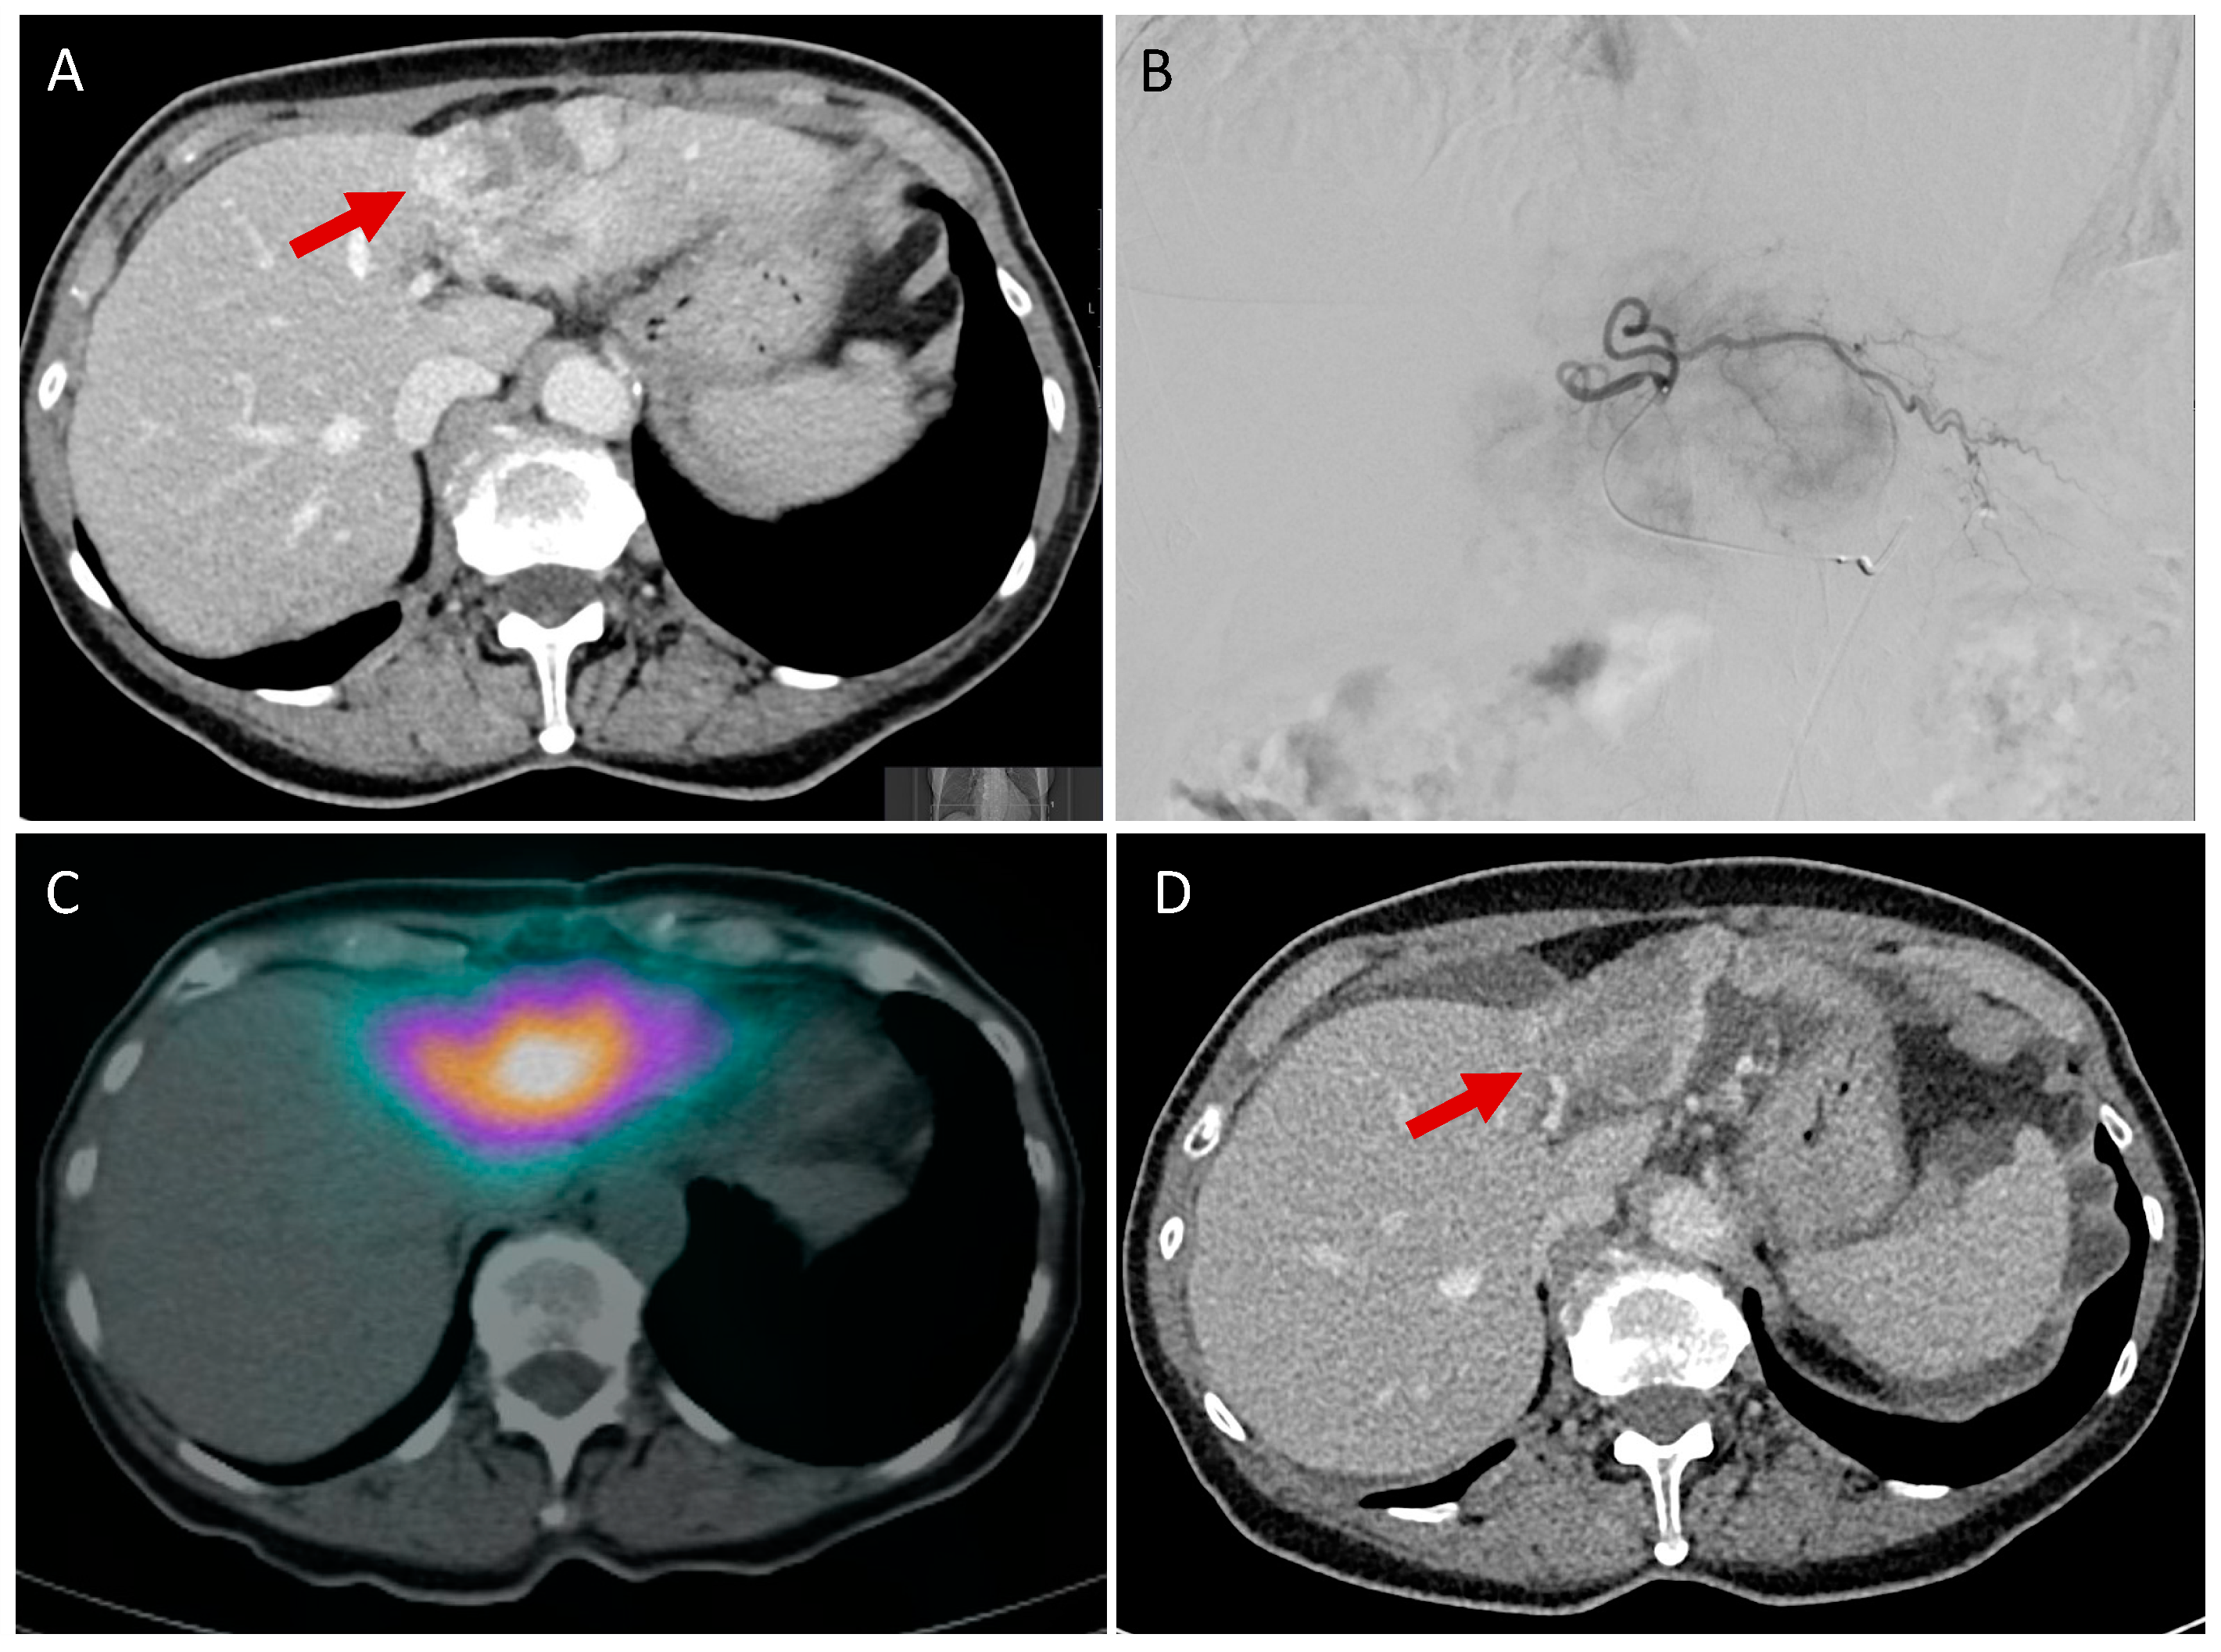

4. Selective Internal Radiotherapy (SIRT)